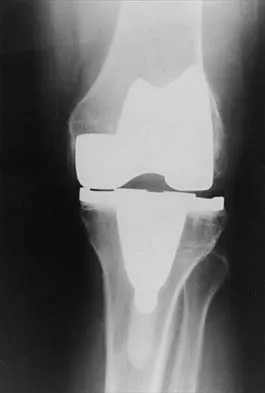

A 75-year-old woman who fell on her right knee now reports pain and is unable to bear weight. History reveals that she underwent total knee arthroplasty on the right knee 6 years ago. Radiographs are shown in Figure 5. Management should now consist of

Explanation

The radiographs show a loose femoral component with an associated medial condyle distal femoral fracture. The treatment of choice is open reduction and internal fixation with revision of the femoral component because of the femoral component loosening. Moran MC, Brick GW, Sledge CB, et al: Supracondylar femoral fracture following total knee arthroplasty. Clin Orthop 1996;324:196-209. McLaren AC, DuPont JA, Schroeber DC: Open reduction internal fixation of supracondylar fractures above total knee arthroplasties using the intramedullary supracondylar rod. Clin Orthop 1994;302:194-198.